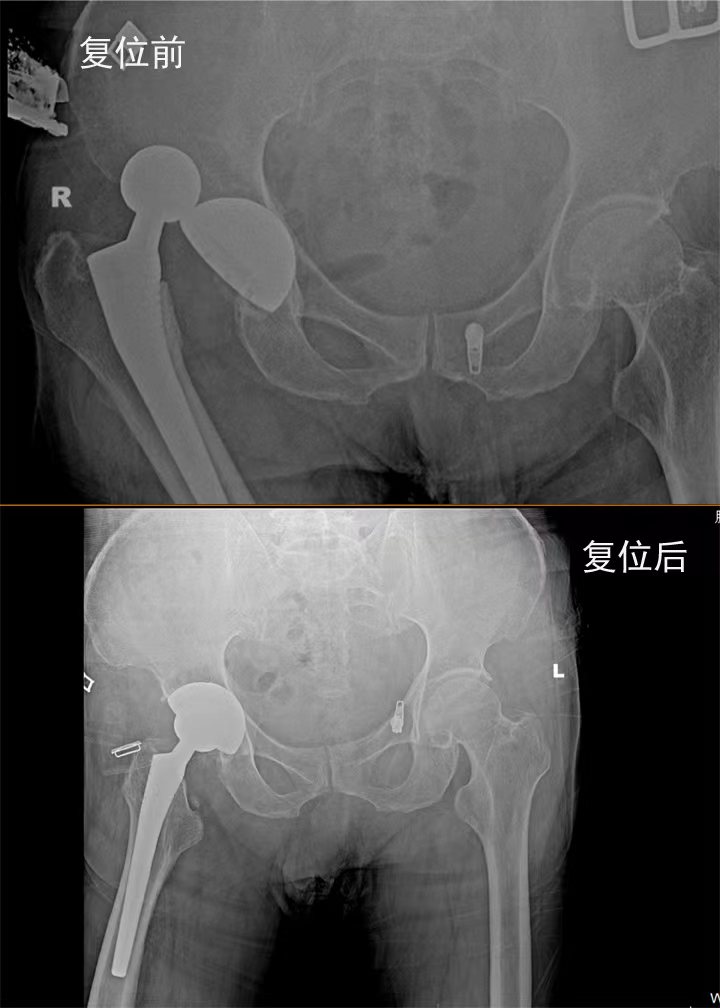

梁氏正骨-梁光兴正骨案例